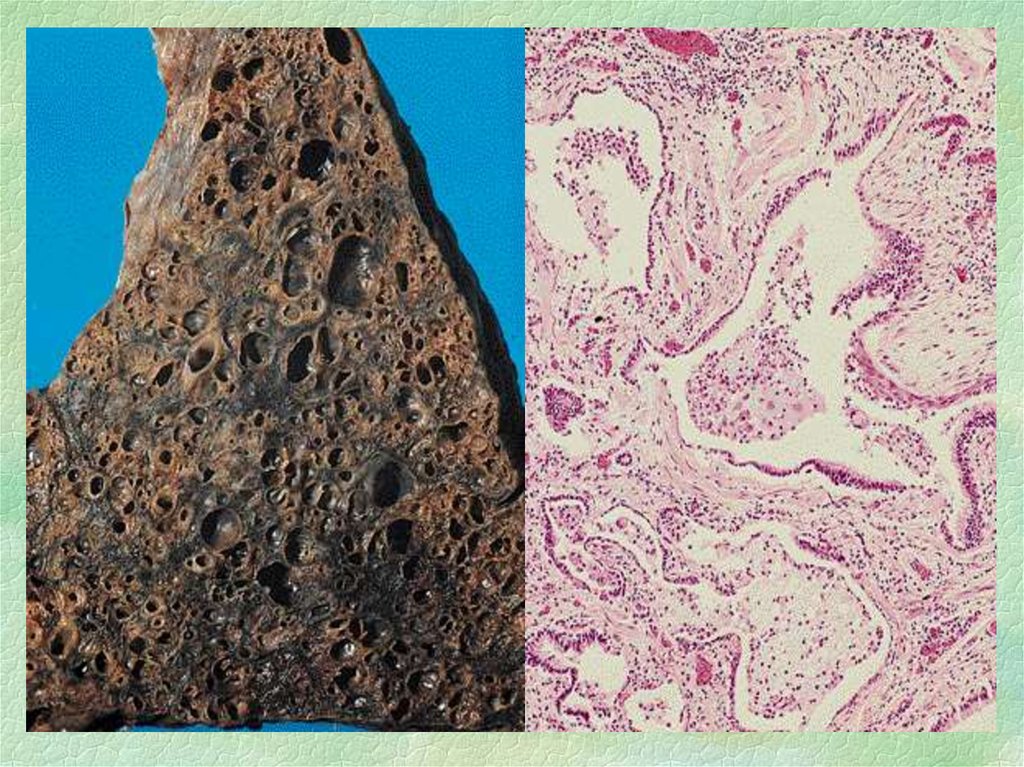

Карнификация Легкого: Микропрепараты и Диагностика

Раздел: Калейдоскоп образов